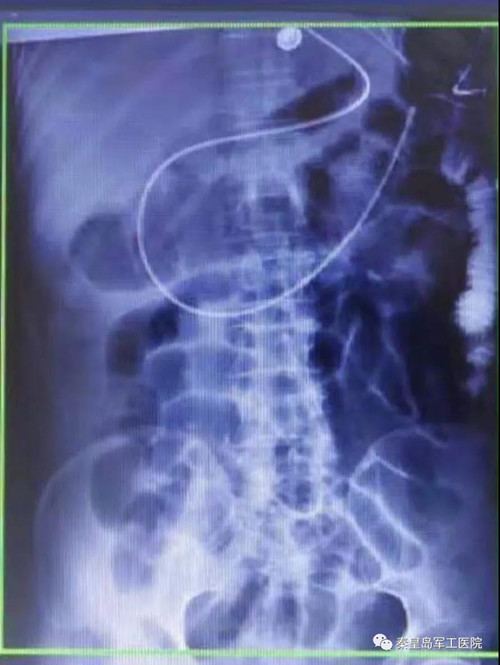

为提高危重症患者置管成功率,王秋艳主任与姚明慧护士长配合,通过床旁超声引导下成功进行鼻肠管的置入。床旁超声被喻为看得见的“听诊器”,在重症医学科的应用日益广泛。该技术利用超声优势,在床旁进行实时引导,准确通过幽门后进行肠内置管。

传统的鼻肠管置入多采用盲插或在介入、x线、胃镜引导下实施,x线及介入引导置管需转运患者,流程相对繁琐。胃镜及介入引导下置管成功率高,但操作需专业人员进行。

相比传统方法,超声引导更加安全稳定,无副作用,置管成功率高。通过超声评估胃排空功能,测量胃残余量等优势,可以尽快给足营养支持,更好的保证患者安全,有效节省人力资源。